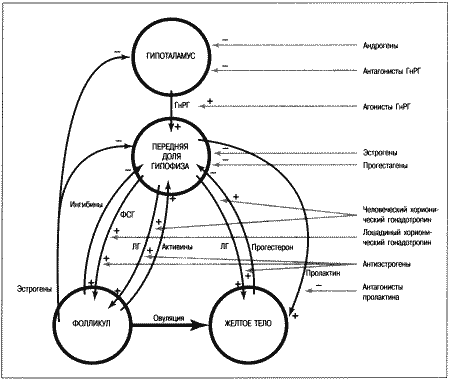

ОБЩИЕ СВЕДЕНИЯ ОБ ЭСТРАЛЬНОМ ЦИКЛЕ

Эстральный цикл представляет собой последовательность взаимосвязанных изменений, происходящих как в яичниках, матке, влагалище, так и в поведении животного. Подобные изменения, характерные для всех млекопитающих, обеспечивают созревание яйцеклеток и внутриматочное развитие эмбрионов. У большинства небеременных самок домашних животных эстральный цикл включает следующие стадии: эструс — период, когда созревшие яйцеклетки находятся в маточных трубах, а половая рецептивность повышает вероятность оплодотворения; диэструс — период подготовки организма к беременности. Если оплодотворения не произошло, наблюдается возврат к проэструсу, во время которого возобновляется развитие фолликулов, приводящее к новому эструсу и соответственно к половой охоте. У некоторых животных — свиней, крупного рогатого скота и лошадей — эструс возобновляется в среднем каждые 3 недели, но в случае беременности наблюдается достаточно продолжительный диэструс, необходимый для ее развития.

Цикл домашней собаки во многом отличается от этой общей схемы. Во-первых, его продолжительность составляет не менее 5 месяцев; во-вторых, беременность развивается в период нормального диэструса, но не продлевает его; в-третьих, между циклами независимо от наличия или отсутствия беременности наступает так называемый анэструс, т. е. продолжительный период относительного покоя яичников. Указанные особенности эстрального цикла суки отражены в специфической терминологии, требующей некоторых пояснений. Поскольку у большинства видов проэструс очень короткий, его длительностью, как правило, пренебрегают. Термин «диэструс» (буквально «между эструсами») часто, хотя и некорректно используют для обозначения межэстрального интервала у собак. Однако если у других млекопитающих этот интервал включает лютеиновую фазу и фазу проэструса, то у сук он включает не только лютеиновую фазу, но также и весьма продолжительный анэструс; исходя из этого лютеиновую фазу предпочтительнее обозначать как «метэструс», а не «диэструс».

Несмотря на указанные различия, эстральный цикл у сук регулируется теми же эндокринными процессами, что и у других видов животных.

• Основной контроль обеспечивают гипоталамус и гипофиз;

• Яичники вырабатывают стероидные гормоны — эстрогены (главным образом эстрадиол) и прогестерон;

• Половые гормоны воздействуют на репродуктивный тракт, добавочные половые железы и участки мозга, управляющие репродуктивным поведением.

Настоящая глава знакомит с общими закономерностями репродуктивного цикла у сук и описывает ситуации, в которых целесообразно проведение эндокринологических исследований и других активных вмешательств.

ПРОЭСТРУС

Стадия проэструса характеризуется развитием фолликулов под влиянием гонадотропных гормонов — лютеинизирующего (ЛГ) и фолликулостимулирующего (ФСГ), выделяемых передней долей гипофиза. Секреция этих гормонов регулируется гипоталамическим гонадотропинрилизинг гормоном (ГнРГ). У собак, так же, как и у других животных, вслед за пиком концентрации эстрадиола возникает (спустя сутки или чуть больше) пик концентрации ЛГ (фиг. 1.1). Таким образом, выброс ЛГ происходит всегда автоматически вслед за повышением активности фолликулов, вырабатывающих эстрадиол, и поскольку овуляция следует за возникающим без внешней стимуляции пиком концентрации ЛГ, ее называют спонтанной. Описанная ситуация разительно отличается от картины, которую можно наблюдать у кошек, для которых характерна индуцированная овуляция: у них выброс ЛГ и овуляция происходят вслед за коитусом. Насколько можно судить, у таких животных эстрадиол не способствует активации секреции ЛГ.

Повышение уровня ФСГ необходимо для стимуляции развития фолликулов и секреции эстрадиола, однако концентрация ФСГ в крови не достигает столь высоких значений, какие наблюдаются при пике ЛГ; это объясняют действием ингибина — белка, секретируемого фолликулами, который избирательно подавляет секрецию ФСГ Тем не менее ФСГ играет важную роль в созревании фолликулов и подготовке их к трансформации в желтые тела после овуляции. Начало трансформации фолликулярных клеток рассматривают как ключевой момент всего цикла, поскольку оно сопровождается преовуляторным повышением секреции прогестерона (фиг. 1.1), которое, по-видимому, играет ведущую роль в пусковом механизме овуляции и подтверждении эструса. Наблюдаемый у собак преовуляторный рост концентрации прогестерона нетипичен для других домашних животных, в частности для жвачных, у которых наступление эструса и овуляции происходит на фоне минимального уровня прогестерона. Однако преовуляторная концентрация прогестерона у собак все же относительно низка, и следует помнить, что назначение высоких доз прогестагенов в период проэструса вызывает отсрочку эструса и овуляции.

Установление роли пролактина для поддержания желтых тел после 30 дня привело к многочисленным попыткам искусственно сократить продолжительность метэструса и индуцировать эструс назначением стимуляторов дофамина (бромокриптина, каберголина, метерголина), применение которых рассмотрено в 16 главе.

Изменения секреции пролактина могут послужить основанием для других объяснений анэструса у сук. Так, концентрация пролактина повышается в период метэструса и в начале анэструса, особенно при беременности. Пролактин обеспечивает лактацию в период анэструса у собак, как и у других видов (свиноматок, кобыл). Этот гормон вызывает снижение чувствительности яичников к гонадотропинам у других видов животных, однако у сук не выявлена последовательная временная корреляция между снижением концентрации пролактина и повышением уровня ЛГ в начале проэструса. При назначении агонистов дофамина (препаратов, подавляющих секрецию пролактина) на стадии метэструса или анэструса концентрация пролактина в плазме крови снижается, соответственно сокращается анэструс.